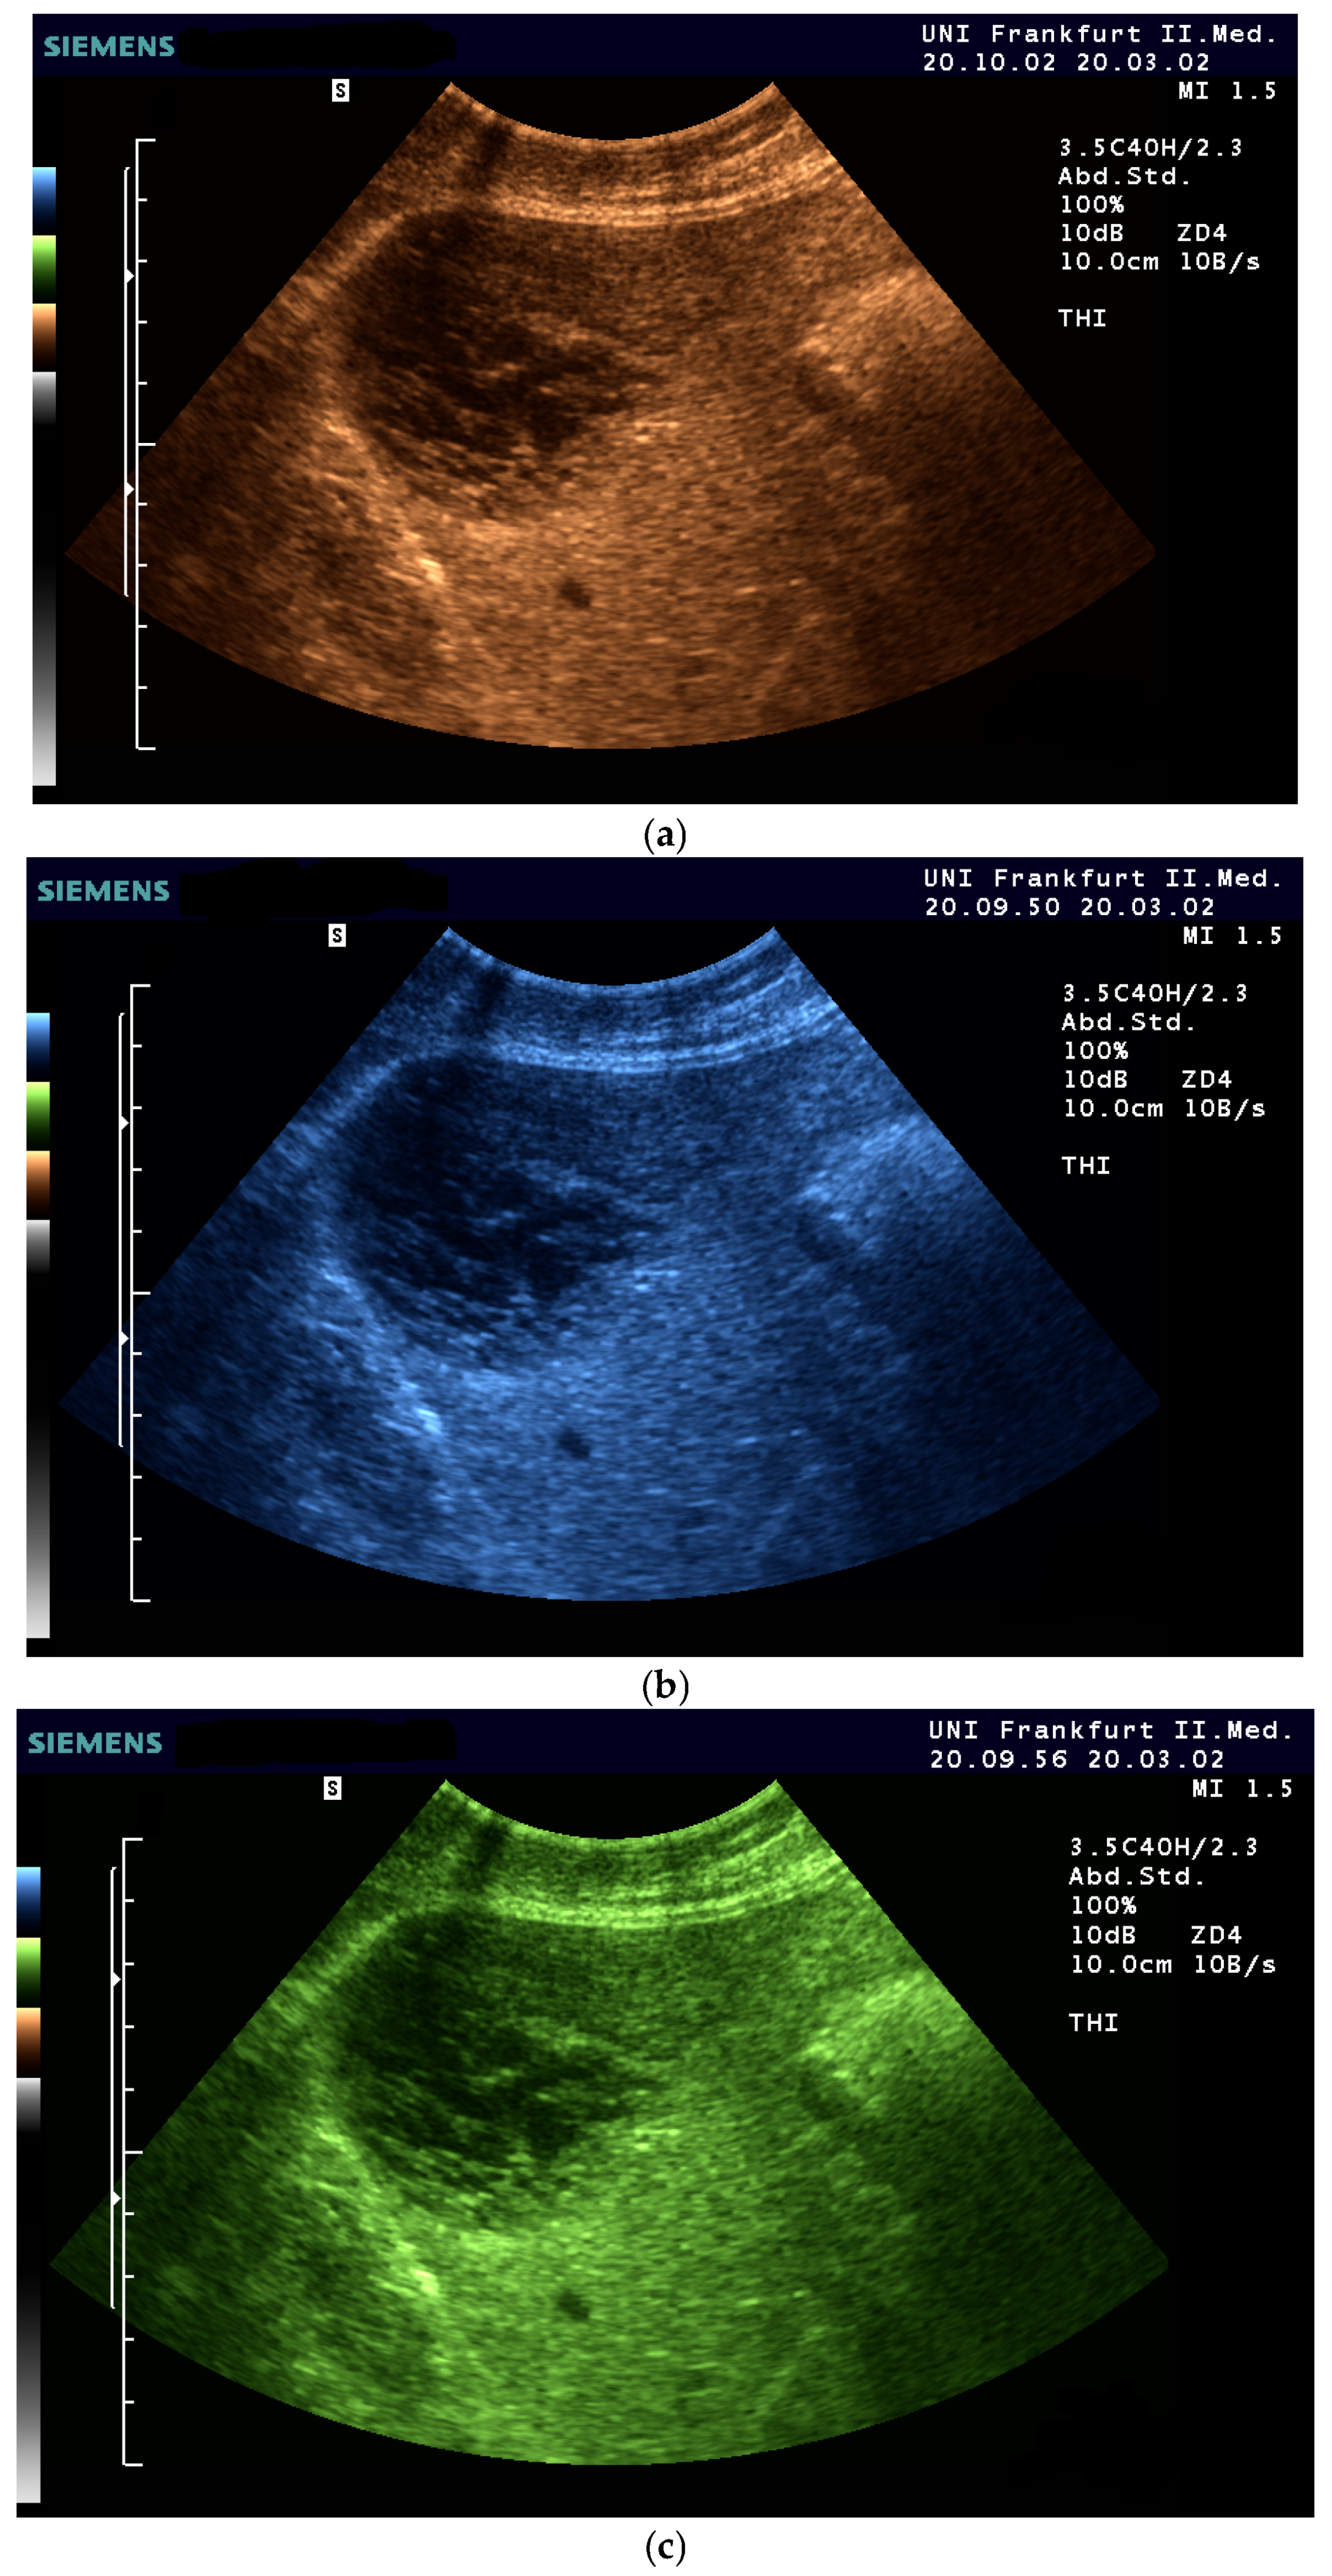

- Fischer, T.; Filimonow, S.; Taupitz, M.; Petersein, J.; Beyersdorff, D.; Bollow, M.; Hamm, B. [Image quality and detection of pathology by ultrasound: Comparison of B-mode ultrasound with photopic imaging and tissue harmonic imaging alone and in combination]. Rofo 2002, 174, 1313–1317. [Google Scholar] [CrossRef] [PubMed]

| Color | Advantages |

|---|---|

| Sepia (Yellow-Brown) | Mimics familiar tones from black-and-white photography |

| Enhances contrast while preserving anatomical detail | |

| Offers intuitive brightness mapping (lighter tones = more echogenic areas) | |

| Preferred by students and experts alike | |

| Blue | Provides excellent depth perception |

| Reduces visual fatigue by avoiding glare and high saturation | |

| Often favored by experienced examiners for high-resolution detail | |

| Facilitates alertness and performance on tasks requiring sustained attention | |

| Green (muted tones) | Offers a balanced hue that avoids excessive saturation |

| Enhances intermediate echogenicity levels without causing artifacts | |

| Especially helpful for liver and parenchymal tissue imaging |